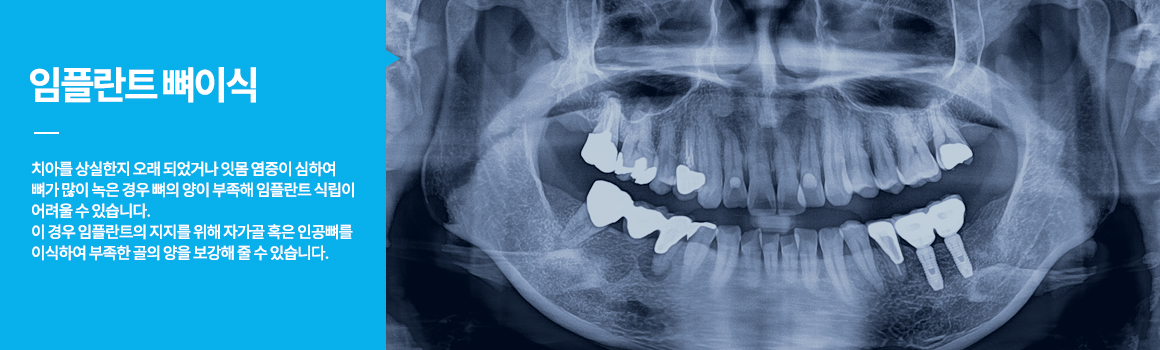

• 임플란트뼈이식